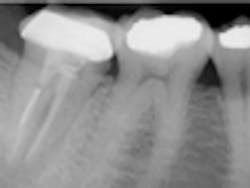

Fig. 1 — Tooth No. 31 referred for endodontic evaluation. After evaluation, the endodontist deemed this tooth hopeless. Clinical factors considered were 1 mm of depressability and a 10 mm probing depth on the straight lingual. Radiographic factors included evidence of excessive coronal flaring, canal transportation, and a fractured post instrument in the distal canal. Extraction and implant therapy was suggested to the patient.There are many benefits to preserving one’s natural dentition vs. extraction and implant therapy. When performed to the standard of care, endodontic therapy provides patients with a long-term result and a shorter mean time to restoration.1 Time to restoration is also reduced relative to implant therapy.2 In addition, endodontic therapy provides patients with a service that maintains the periodontal ligament, or PDL. The PDL is crucial to proprioception in order to maintain occlusal feedback and avoid damage to the temperomandibular joint. Preservation of the natural periodontal complex also allows for future orthodontic movement if needed, whereas an osseointegrated implant is an ankylosed structure that may impede orthodontic therapy. The negative psychological implications of tooth loss is never experienced by a patient who keeps his or her own dentition, and the long-term satisfaction rate is just as high relative to implant therapy3 (Figs. 2 and 2a).